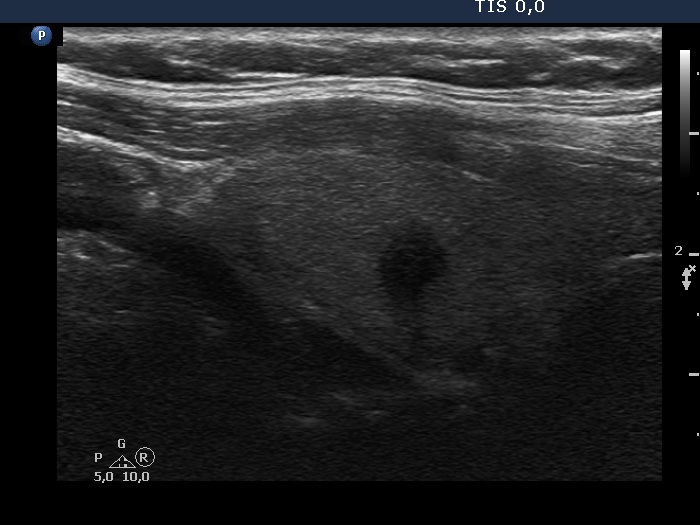

Graves' disease - case 1147

Follow-up examination six years after the first visit (ultrasonographic picture 3)

Right lobe, another longitudinal scan.